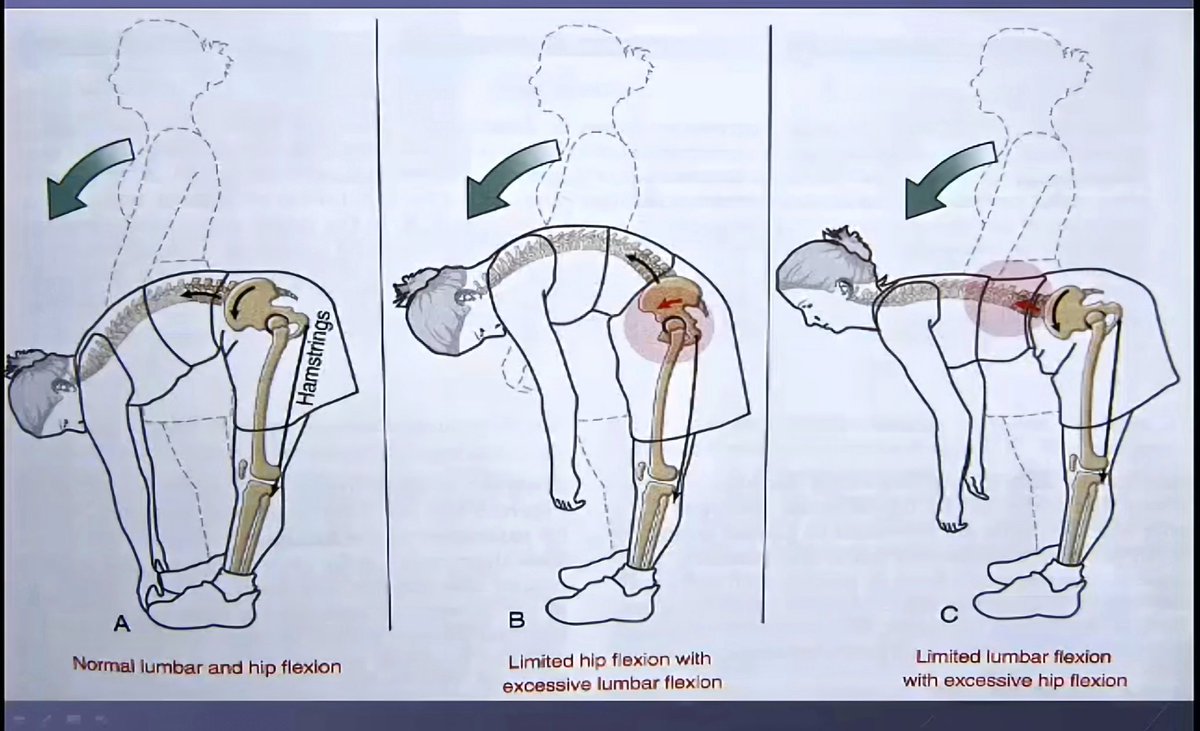

💢 ايش علاقة ألم أسفل الظهر مع العضلات الخلفية. ⁉️

وليش أحيانا تحس الألم في ظهرك ولكن المشكلة الأساسية عندك تكون في العضلات الخلفية وليس في الفقرات او عضلات أسفل الظهر.‼️ 🤷🏻♂️

💢 ايش علاقة ألم أسفل الظهر مع العضلات الخلفية. ⁉️

وليش أحيانا تحس الألم في ظهرك ولكن المشكلة الأساسية عندك تكون في العضلات الخلفية وليس في الفقرات او عضلات أسفل الظهر.‼️ 🤷🏻♂️